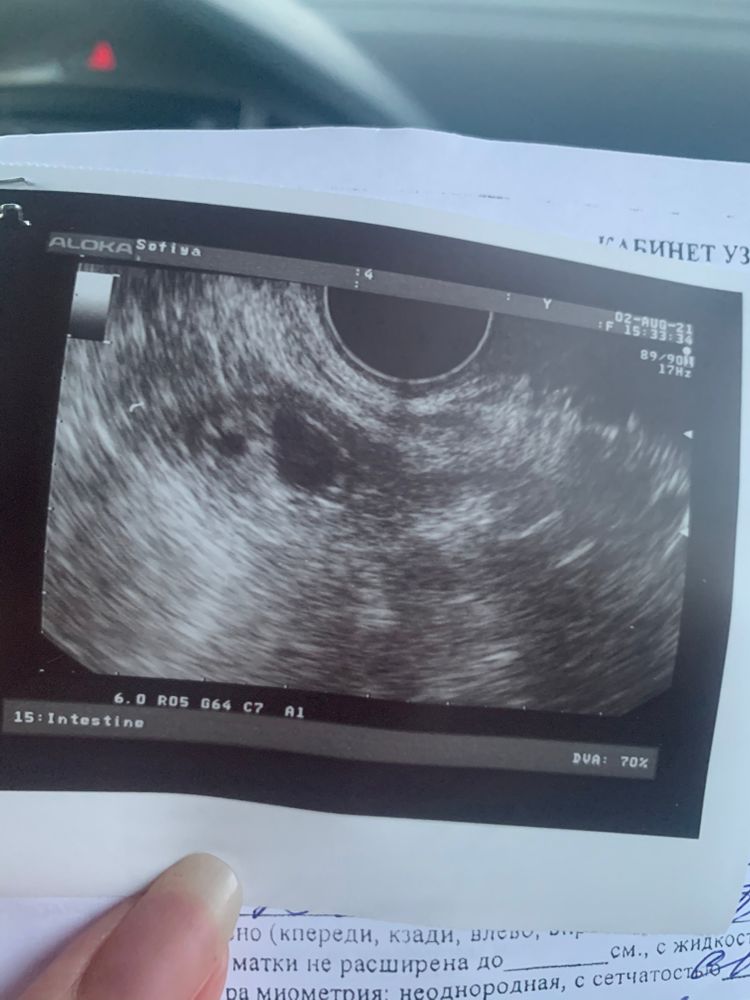

Фото узи и тесты выкину , но оставлю фото тут...